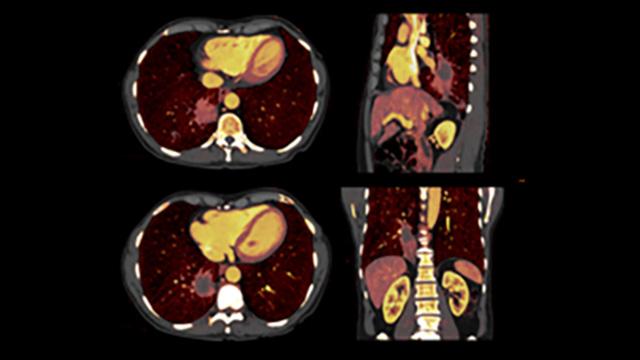

Siemens HealthineersのフォトンカウンティングCT「NAEOTOM Alpha」シリーズは、X線の個々の光子をエネルギー別に検出する技術を用いて高感度なX線検出や高空間分解能、低線量撮影技術、スペクトラル情報の活用を可能にすることにより、画像診断のみならず、放射線治療の治療計画作成にも新たな価値を提供します。

- スペクトラル情報による組織識別と線量計算精度の向上: X線のエネルギー(スペクトル)情報を活用することで、組織や物質の違いを明確に識別でき、腫瘍の性状評価にも応用可能です。スペクトラル情報を活用したイメージングにより、組織の性状だけでなく、電子密度や実効原子番号などの組織情報を定量的に取得できるため、線量計算に必要な物理特性の精度が向上します。不確実性を低減し、線量計算精度向上にも貢献します。